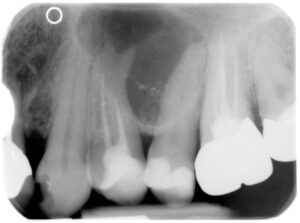

Hier sieht man das Problem:

Auf dem ersten Röntgenbild hat der zweite Zahn von links eine Wurzelfüllung. Trotz Wurzelbehandlung und -füllung weist dieser Zahn eine ausgeprägte Zyste auf. Zum besseren Verständnis ist diese auf der zweiten Abbildung grün umrandet. Durch das Zystenwachstum wurden die Wurzelspitzen des ursächlichen Zahnes und des Zahnes rechts davon auseinander gedrängt.